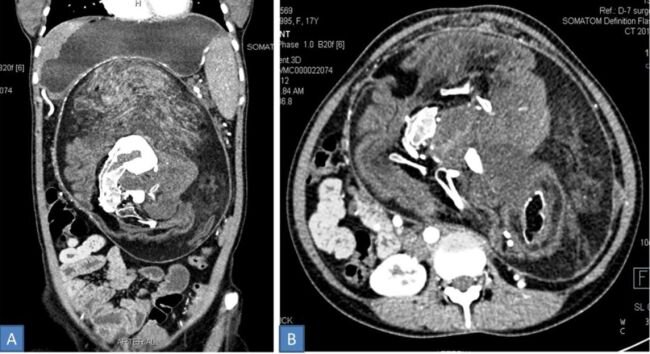

Согласно новому сообщению, у подростка в Индии была обнаружена странная масса костей, зубов и «волосатого сырного материала» в ее животе. Это был ее собственный "близнец", растущий внутри нее, в результате крайне редкого состояния, называемого " плод в плоде ". Согласно отчету, опубликованному 12 августа в журнале BMJ Case Reports, 17-летняя девочка обратилась к врачу после того, как у нее образовался опухоль в животе, который постепенно увеличивался в размерах в течение последних пяти лет . Подросток сказал врачам, что иногда она испытывала боль в животе и чувство сытости, даже когда она не ела много еды. КТ показала, что у подростка была большая масса в животе, которая, по-видимому, содержала множественные кости, «напоминающие форму позвонков, ребер и длинных костей», пишут авторы. Врачи поставили диагноз подростку с плодом у плода, состояние, которое, по оценкам, встречается только у 1 из 500 000 человек во всем мире. Новый случай еще более необычен, потому что он был диагностир